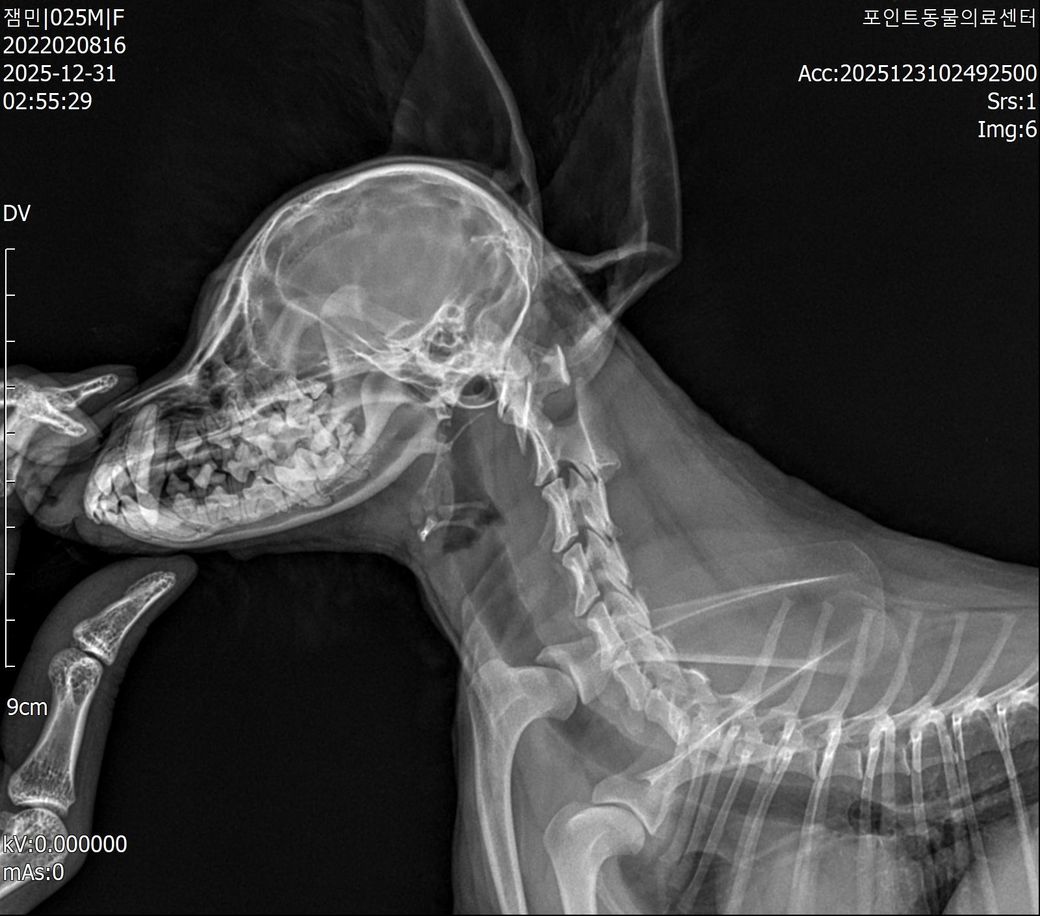

척수증, 척수연화증 판정 받았습니다만, 제가 저희 아이 CT사진을 확인했을때 환축추아(AAI)로도 의심해볼 수 있을거같은데 도움이 필요합니다,,

■ 반려동물 질환 : 척수증, 척수연화증, 환축추아(AAI)

현재까지의 내용입니다, 현재도 고개만 움직일 수 있으며, 팔과 다리는 스스로 움직일 수 없는 상황입니다. (현재 스테로이드 치료 4일차) 다만 제가 검색을 계속 하다보니 저희 강아지 CT 사진을 보아 환축추아(AAI)로도 의심이 되는데 가능성이 있는지 확인 가능하신 분 있으시면 확인좀 부탁드립니다 사진 첨부드립니다..

방사선 사진상 환축추불안(AAI)가능성은 낮아 보입니다. 물론 stress view 등 진단을 위한 standard view가 아니기 때문에 이는 추정이며 환자를 직접 본 주치의 판단이 가장 정확합니다.